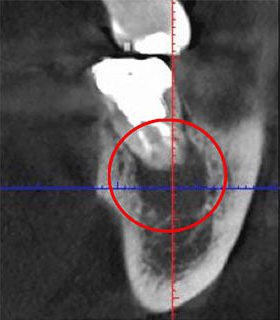

次の画像は、同じ歯をCTとレントゲンで撮影したものの比較です。

左がCT、右がレントゲンとなります。

CT画像(左)では黒い影が見えますが、レントゲン画像(右)にはその影がありません。この黒い影は、歯の根の炎症です。つまり、レントゲンだけで検査していたら、この炎症は見逃されてしまうということです。

CTを使用することで、初期の炎症も見逃すことなく、適切な診断が可能になります。